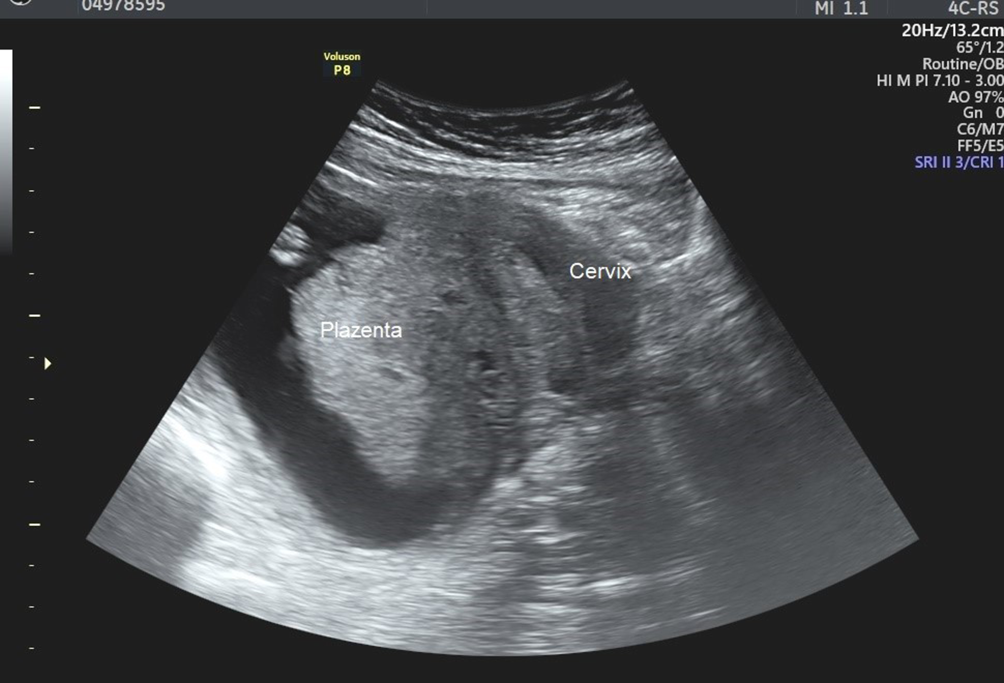

Befund (Abb. 1):

• druckdolenter Unterbauch,

• Entleeren von 1200 ml Urin per Einmalkatheter,

• Spekulum: Zervix schwer auffindbar, schließlich hinter der Symphyse darstellbar,

• transabdominelle Sonographie: intakte Einlingsgravidität entsprechend dem Gestationsalter.

Abb. 1

Sonographischer Befund einer Schwangerschaft bei hinterer Uterussakkulation

„Auflösung“: hintere Sakkulation bei retrovertiert/retroflektiertem Uterus

Sonographisch kann eine Fundusplazenta teilweise als tiefliegende Plazenta falsch interpretiert werden, da der Fundus sich im kleinen Becken befindet. Zudem kann die Zervix als Corpus uteri missinterpretiert werden, sodass eventuell von einer ektopen Schwangerschaft ausgegangen wird.